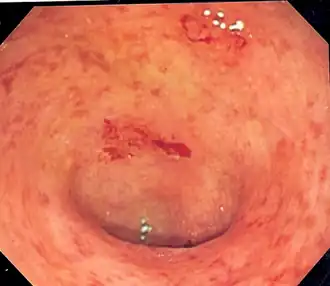

La coloscopie montre typiquement un aspect inflammatoire du côlon, naissant au niveau du rectum et remontant plus ou moins haut de manière continue. Cette continuité des lésions est parfois inconstante[3]. La sévérité de la maladie dépend en partie de son extension.